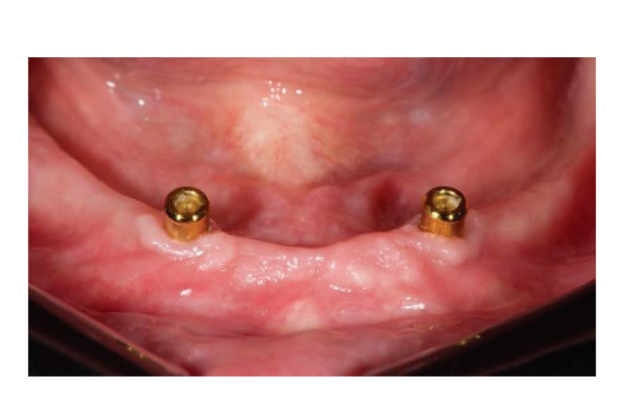

Dopo l'intervento, ai pazienti è stato consigliato di evitare qualsiasi trauma nel sito chirurgico, comprese le procedure di spazzolamento. È stata prescritta una dieta fredda e morbida post-chirurgica. Dopo l'intervento, ai fumatori è stato consigliato di astenersi dal fumo per due settimane. Sono state fornite istruzioni dettagliate per l'igiene orale, inclusa la raccomandazione di sciacquare tre volte al giorno con clorexidina allo 0,12%. Sono stati prescritti analgesici, come 600 mg di ibuprofene o alternative simili, secondo necessità. I punti di sutura sono stati tipicamente rimossi entro un periodo di dieci a quattordici giorni. Secondo un flusso di lavoro precedentemente riportato, le procedure protesiche sono iniziate otto settimane dopo l'inserimento degli impianti. Secondo un protocollo di carico precoce, una nuova dentiera rimovibile completa rinforzata in metallo è stata consegnata in entrambi i gruppi entro quattro settimane dopo l'inserimento degli impianti. Dopo due o tre giorni, gli abutment di guarigione sono stati svitati e gli attacchi sono stati collegati a lato della poltrona alla nuova protesi rimovibile. I pazienti sono stati randomizzati per ricevere attacchi OT Equator® (Rhein’83, Bologna, Italia) nel gruppo di test o attacchi Locator (Zest Anchors LLC) nel gruppo di controllo. I sistemi di attacco randomizzati sono stati posizionati e serrati secondo le istruzioni del produttore. Nel gruppo di test (Figure 1–5), dopo la guarigione gengivale, i più recenti attacchi OT Equator® a basso profilo sono stati avvitati sugli impianti utilizzando il cacciavite quadrato OT Equator®, con un intervallo di coppia di 22–25 Ncm. Le altezze dei manicotti variavano da 0,5 a 7,0 mm, a seconda delle dimensioni della zona di transizione di ciascun impianto, facilmente misurabili utilizzando il misuratore di altezza del manicotto millimetrico a codifica colore (Rhein’83, Bologna, Italia) dopo la rimozione dell'abutment di guarigione. Successivamente, è stato preparato lo spazio necessario per accettare la gabbia in acciaio della sede femminile nella superficie di adattamento della dentiera rimovibile completa mandibolare. Dischi protettivi in silicone (Rhein’83, Bologna, Italia) sono stati posizionati sopra gli attacchi OT Equator®. Cappucci di ritenzione extra-morbidi (giallo, 600 g) sono stati inizialmente inseriti nella sede femminile in acciaio, attaccati a OT Equator®, e infine fissati alla dentiera utilizzando resina acrilica autoindurente. Allo stesso tempo, il paziente ha tenuto le dentiere in occlusione, direttamente a lato della poltrona. Dopo la completa polimerizzazione, la dentiera è stata prelevata e i dischi in silicone sono stati rimossi. L'eccesso di acrilico è stato rifilato e la dentiera è stata rifinita e lucidata. Un mese dopo la consegna delle protesi, i cappucci di ritenzione gialli sono stati sostituiti con un tipo più robusto (rosa, 1200 g).